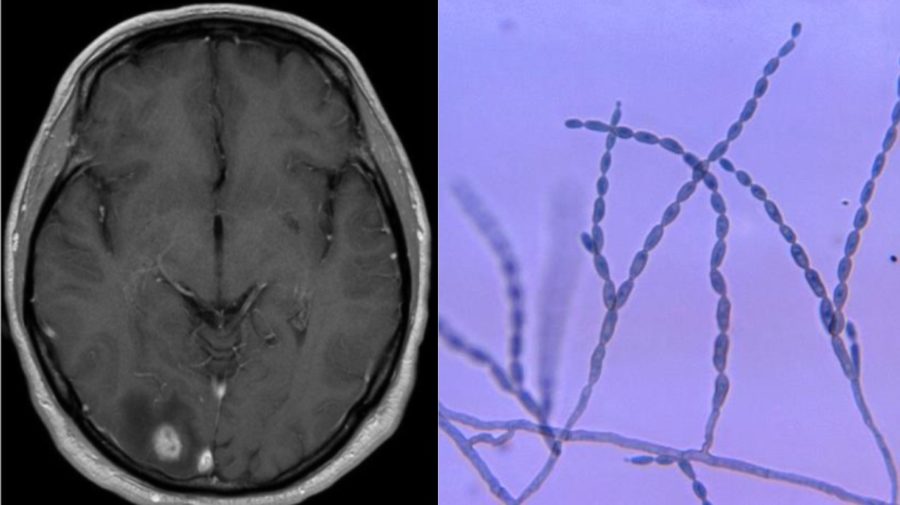

„Lekári boli prekvapení, pretože huba Cladophialophora bantiana je taká vzácna,“ povedal Bottenus pre denník. „Prvé dve biopsie mozgu boli neúspešné, ale tá tretia, namiesto toho, aby našli rakovinu mozgu, na ktorú mali podozrenie, našla na mojom mozgu rastúcu čiernu pleseň. Moja neurochirurgička povedala, že to doslova vidí.“

Lekári neskôr dospeli k záveru, že muž chytil Cladophialophora bantiana, ktorá sa prezýva aj „čierna pleseň“ na výlete v Kostarike.

Čo vieme o Cladophialophora bantiana:

Cladophialophora bantiana alebo C. bantiana je je dematózna huba, o ktorej je známe, že spôsobuje mozgové abscesy u ľudí. Podľa štúdie uverejnenej na webe Národnej lekárskej knižnice Spojených štátov amerických, lekári zaznamenali doteraz len 120 prípadov nákazy „čiernou piesňou“.

Väčšina z nich (70 %) bola zaznamenaná u mužov vo veku do 35 rokov. Často u ľudí so zníženou imunitou. Najviac nákaz bolo zaznamenaných v subtropických oblastiach, ale môže sa vyskytovať aj v miernych klimatických pásmach. Vedci doteraz nevedia, ako vstupuje do tela, myslia si, že cestu do mozgu si môže nájsť prostredníctvom rán a krvou potom putovať až do mozgu. Možná je aj inhalácia prostredníctvom dýchacích ciest človeka.

Úmrtnosť je približne 65 %, pričom v minulosti sa pohybovala až na 100 %. Liečba pozostáva z chirurgického zákroku, ktorý odstráni léziu v mozgu a následnej antimykotickej liečbe, prostredníctvom protiplesňových liekov. Ak sa lézia nedá chirurgicky odstrániť, nasadia sa antimykotiká a iné liečivá. Úspešnosť liečby a nižšia úmrtnosť je preukázaná pri pacientoch, ktorým sa podarilo odstrániť léziu. Všetci pacienti, ktorí nepodstúpili žiadnu liečbu, umreli.